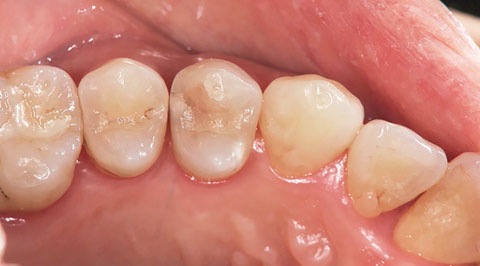

症例1-1 54のメタルインレー下に二次カリエスを認めた。間接法と直接法による修復のメリットとデメリットを説明し、患者はカリエス除去後に直接法によるCR修復を選択した。

症例1-2 メタルインレーを除去すると、二次カリエスを認めることが多くの場合に見受けられる。う蝕検知液等を用い、カリエスを確実に除去する。その際、可及的に歯質の保存を図る。